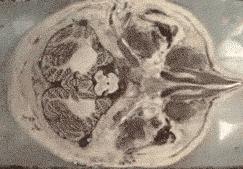

磁共振检查又称磁共振成像(简称MRI),其基本原理是将人体置于特殊的磁场中,用无线电射频脉冲激发人体内氢原子核,引起氢原子核共振。 在停止射频脉冲后,氢原子核按特定频率发出射电信号,并将吸收的能量释放出 来,被体外的接收器收录,经电子计算机处理获得图像, 称为核磁共振成像。

核磁共振所获得 的图像非常清晰精细,可以清楚地分辨肌肉、肌腱、筋 膜、脂肪等软组织结构,提高 了影像对疾病诊断的准确性。对检测脑内血肿、脑外血肿、脑肿瘤、颅内动脉瘤、动静脉血管畸形、脑缺血、椎管内肿瘤、脊髓空洞症和脊髓积水等颅脑常见疾病有效,对腰椎间盘后突、腰椎椎管狭窄、原发性肝癌等疾病的检查也很有效。